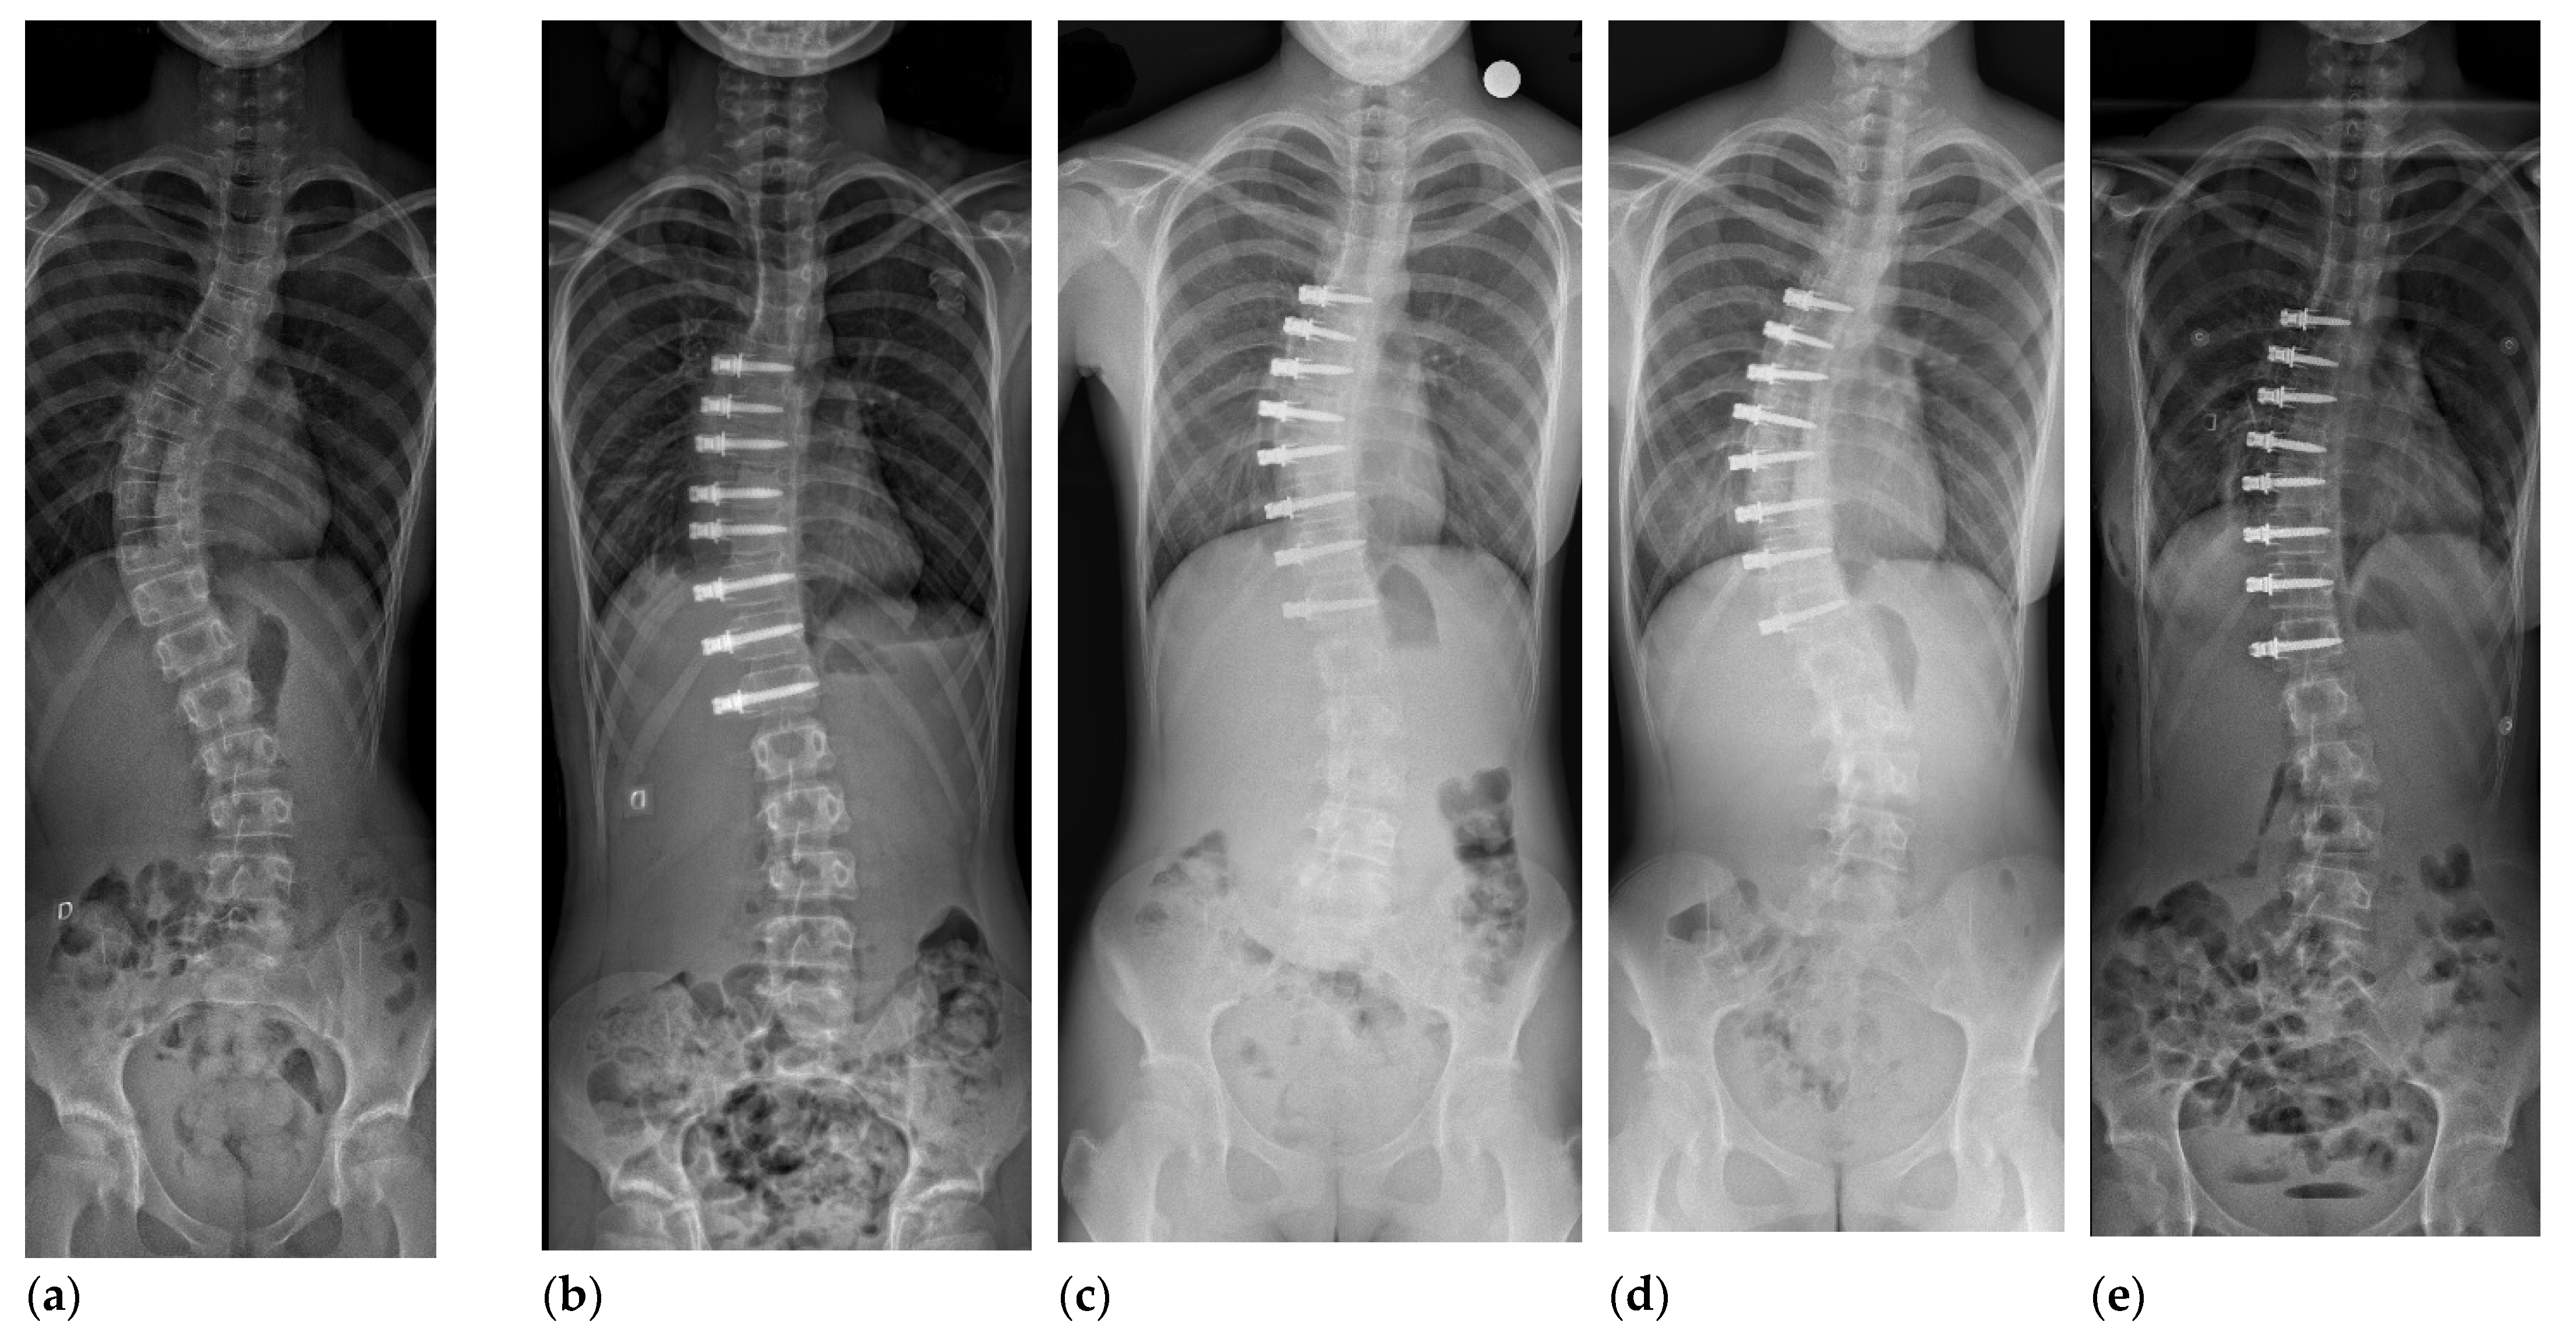

3. Anterior Vertebral Body Tethering

4.1. Curve Correction after AVBT in Thoracic Curves